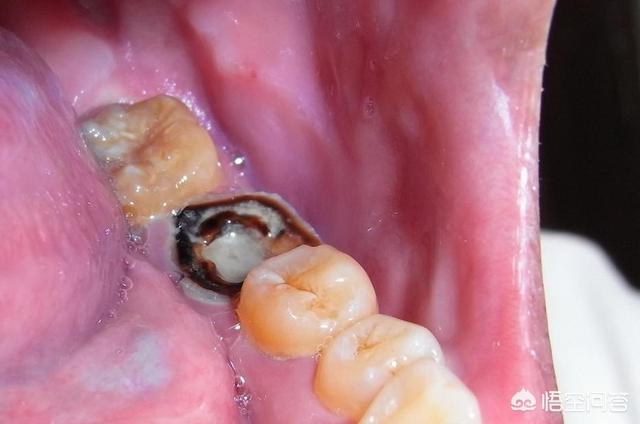

Les deux grosses dents pourries dans le coin inférieur de la bouche gauche indiquent que les dents sont gravement cariées par des bactéries, que la pulpe peut être infectée par des lésions bactériennes, ce qui déclenche une crise aiguë d'inflammation de la pulpe, que les dents ne peuvent pas être arrachées même si elles sont pourries, parce que les racines des dents sont toujours là et qu'elles peuvent être traitées sur les dents.

Par exemple, le plus courant est le traitement du canal radiculaire, en cas de pulpite ou de nécrose pulpaire, qui consiste d'abord à retirer la pulpe malade, ce qui permet de résoudre le problème des maux de dents et, ensuite, de faciliter la restauration dentaire en portant des couronnes en porcelaine.